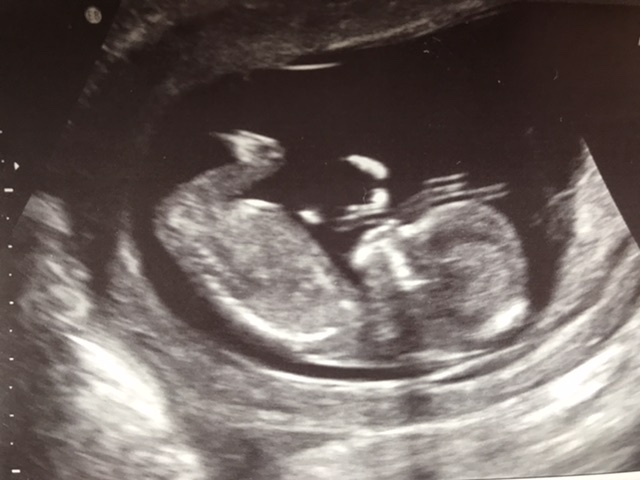

Ok, enough venting! Here are my scan pics from 13weeks.

Attachment 42925Attachment 42926Attachment 42927